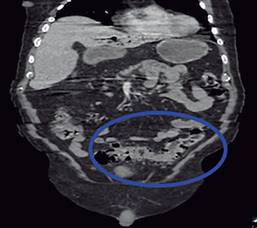

Masculino de 77 años con antecedentes de diabetes mellitus 2 e hipertensión arterial sistémica de larga evolución, antecedentes quirúrgicos de colecistectomía laparoscópica hace seis años y cateterismo cardiaco por cardiopatía isquémica crónica. Inicia su padecimiento actual 10 días previos a su ingreso con cuadro de dolor abdominal difuso en cuadrantes inferiores, así como ataque al estado general acompañado de astenia e hiporexia. Fue manejado por facultativo externo con antibioticoterapia. A su llegada al Servicio de Urgencias se presenta con taquicardia y tendencia a la hipotensión acompañado de alteración del estado de alerta. A la exploración física se palpa plastrón inflamatorio en cuadrante inferior izquierdo que despierta dolor a la manipulación del mismo, sin embargo, no hay datos de irritación peritoneal, sus laboratoriales con leucocitos 13,400 mm3, neutrofilia 92.9% y lactato de 3.9 mmol/l. Se solicita tomografía abdominopélvica contrastada en donde se muestra trombosis de la vena porta (Figura 1), neumatosis portal (Figura 2) y enfermedad diverticular (Figura 3), por los hallazgos anteriores se da manejo inicial con soluciones intravenosas y antibioticoterapia empírica de amplio espectro con piperacilina-tazobactam 4.5 g IV cada 8 horas, posterior al manejo estabilizador se realiza laparotomía exploradora, en donde se realiza sigmoidectomía y colostomía terminal debido a los hallazgos de perforación diverticular (Figuras 4 y 5) y plastrón inflamatorio purulento en el mesosigmoides con especial distribución en el trayecto de la vena mesentérica inferior, se toma cultivo y se maneja el posoperatorio en terapia intensiva, se deja antibioticoterapia dirigida a E. coli. Se calcula nutrición parenteral total y se inicia terapia anticoagulante con enoxaparina 60 mg subcutáneos (SC) cada 12 horas. El paciente cursó con evolución clínica favorable gracias al manejo multidisciplinario que se brindó. Egresó a la semana del procedimiento quirúrgico sin complicación alguna, se cita a consulta externa una semana después de su egreso tolerando vía oral con estoma funcional y con la herida afrontada. El reporte de histopatología reveló enfermedad diverticular complicada.